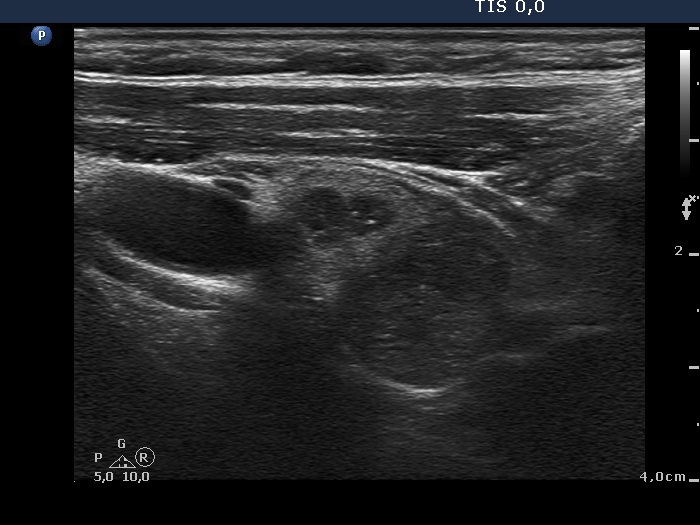

Benign hyperplastic nodule (histological diagnosis) - case 2 |

Hashimoto's thyroiditis without any nodule (histological diagnosis) - case 1520 |

The bright granules lack the dorsal narrowing tail and there are no coexisting similarly bright lines, therefore these granules correspond to punctate echogenic foci.

The coexistence of tiny punctate granules and similarly bright lines is the hallmark of connective tissue. There is a brighter and relatively large granule in the ventral small lesion in the upper image which might be either a punctate echogenic focus or a sign of fibrotic changes.